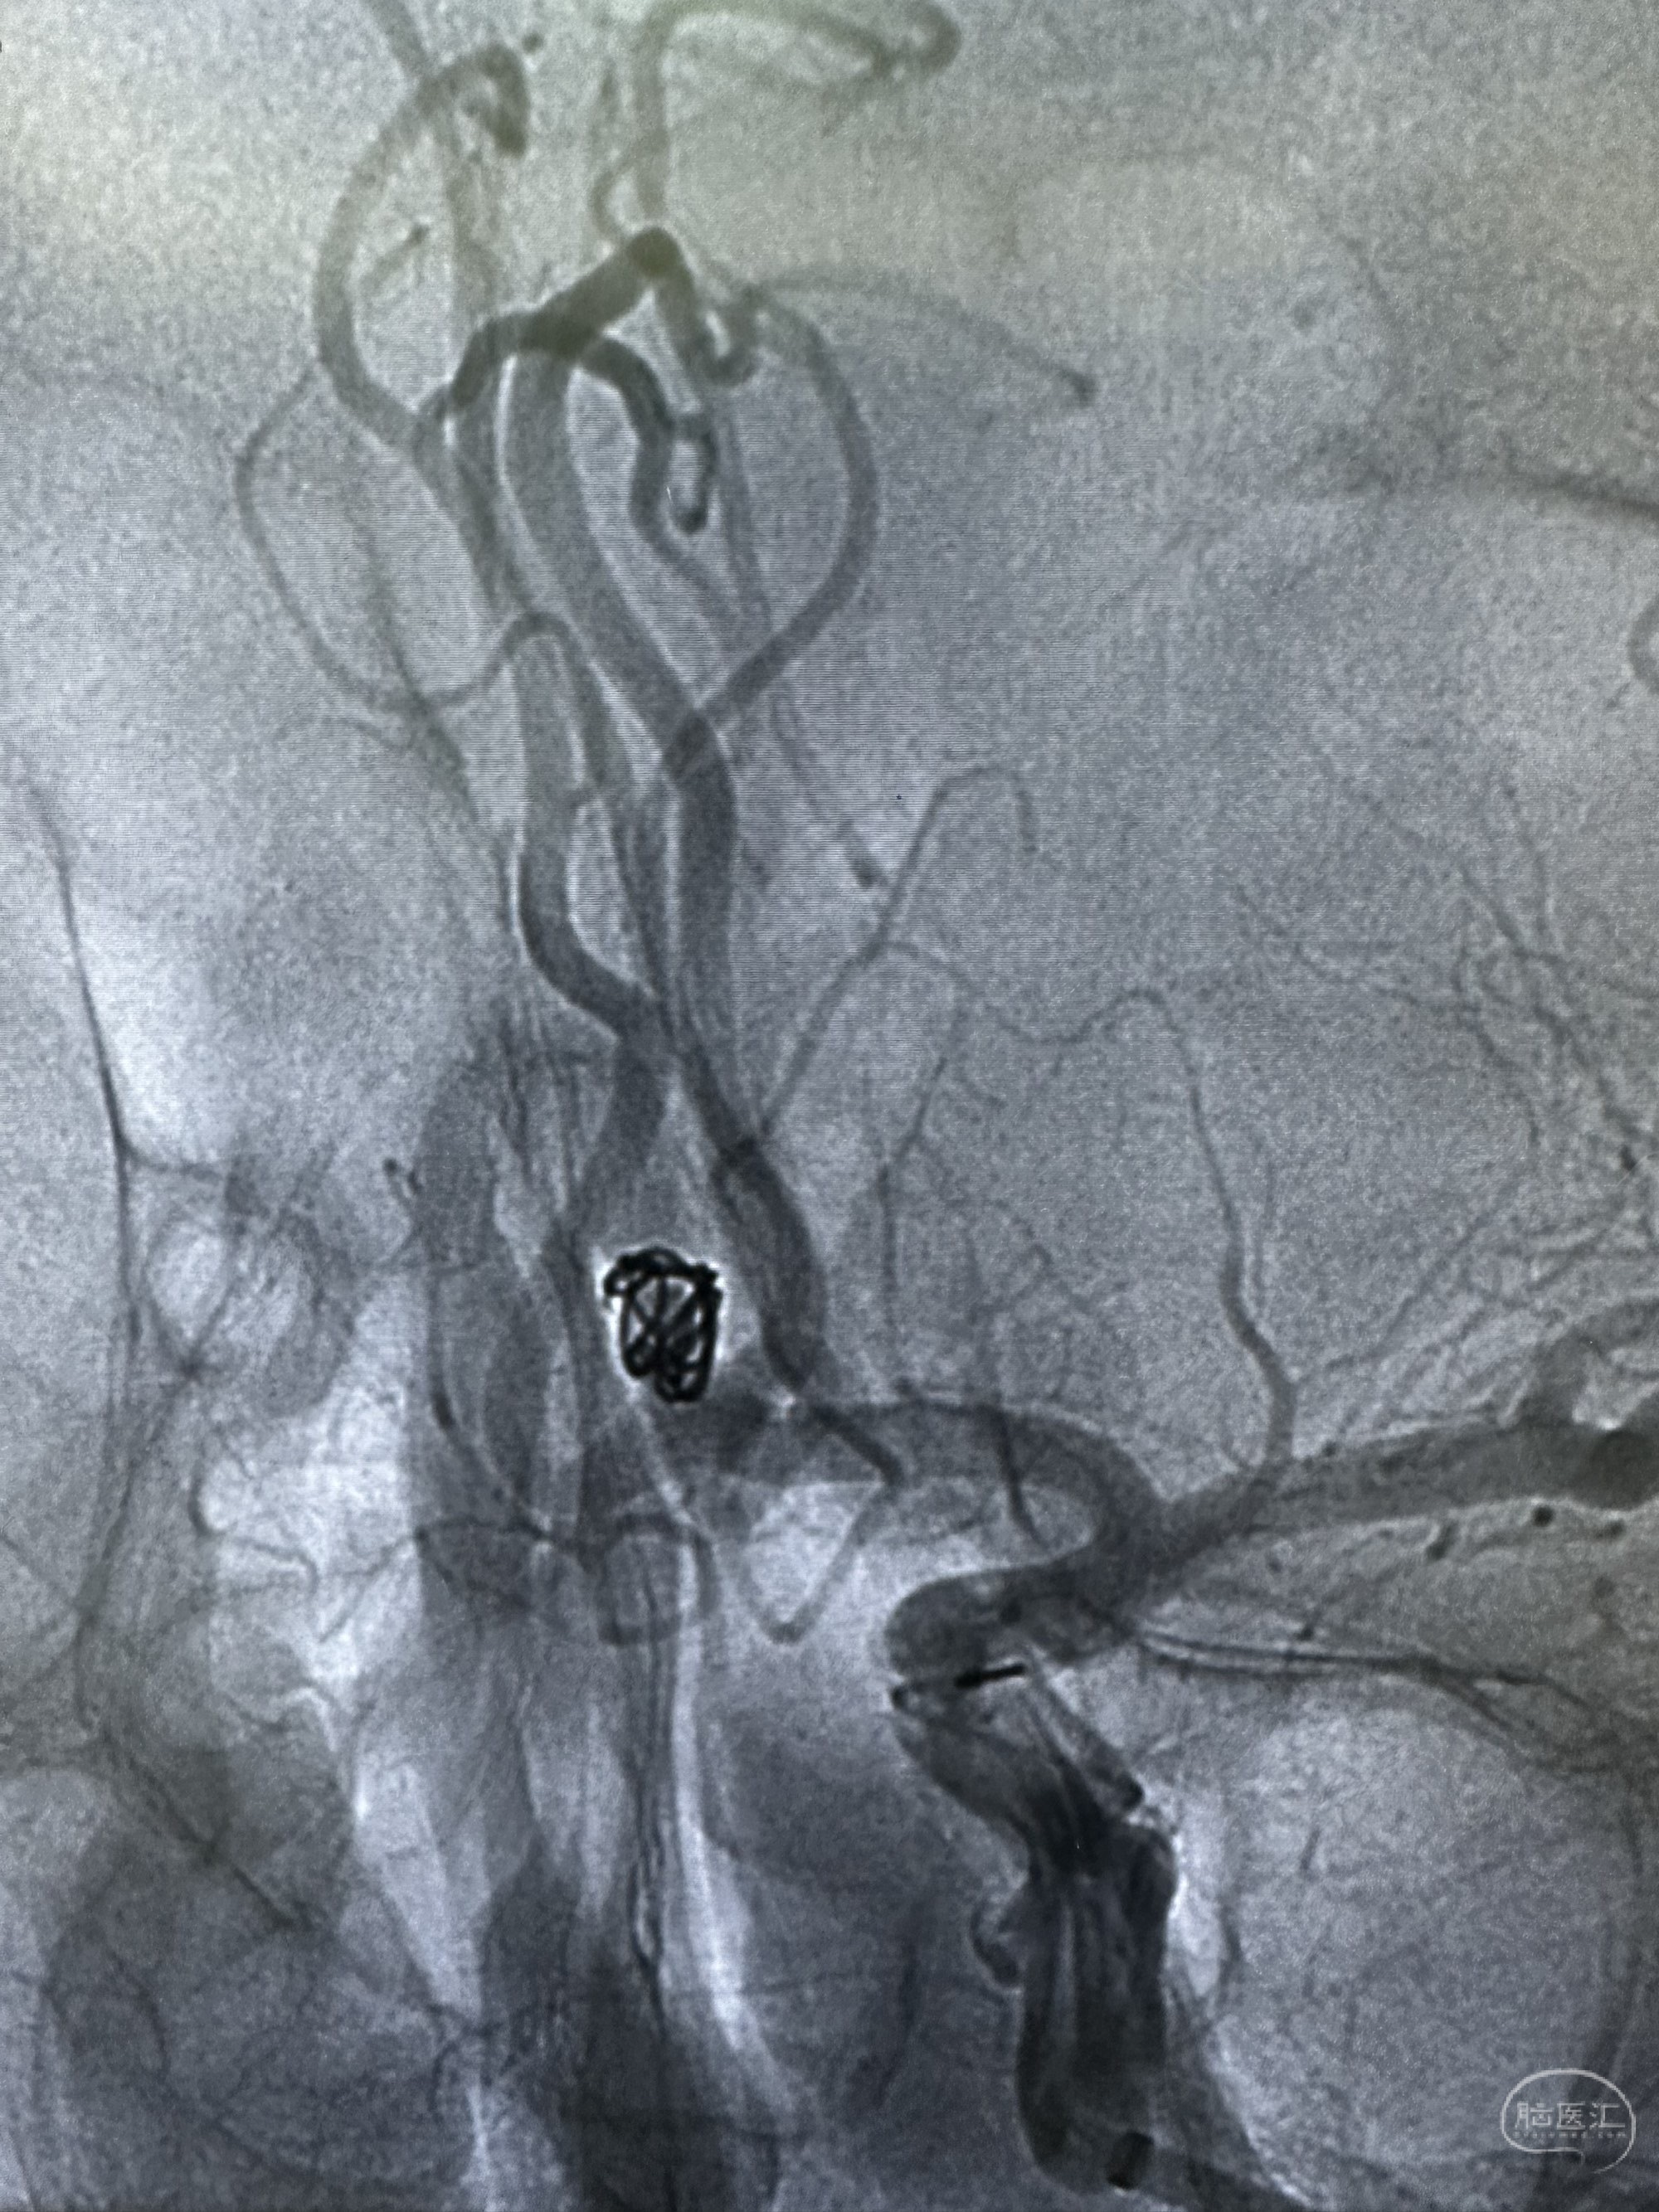

工作角度,选择Neuromax90加上6f的银蛇115

第一枚圈选择4*8的target 3D

圈的形态